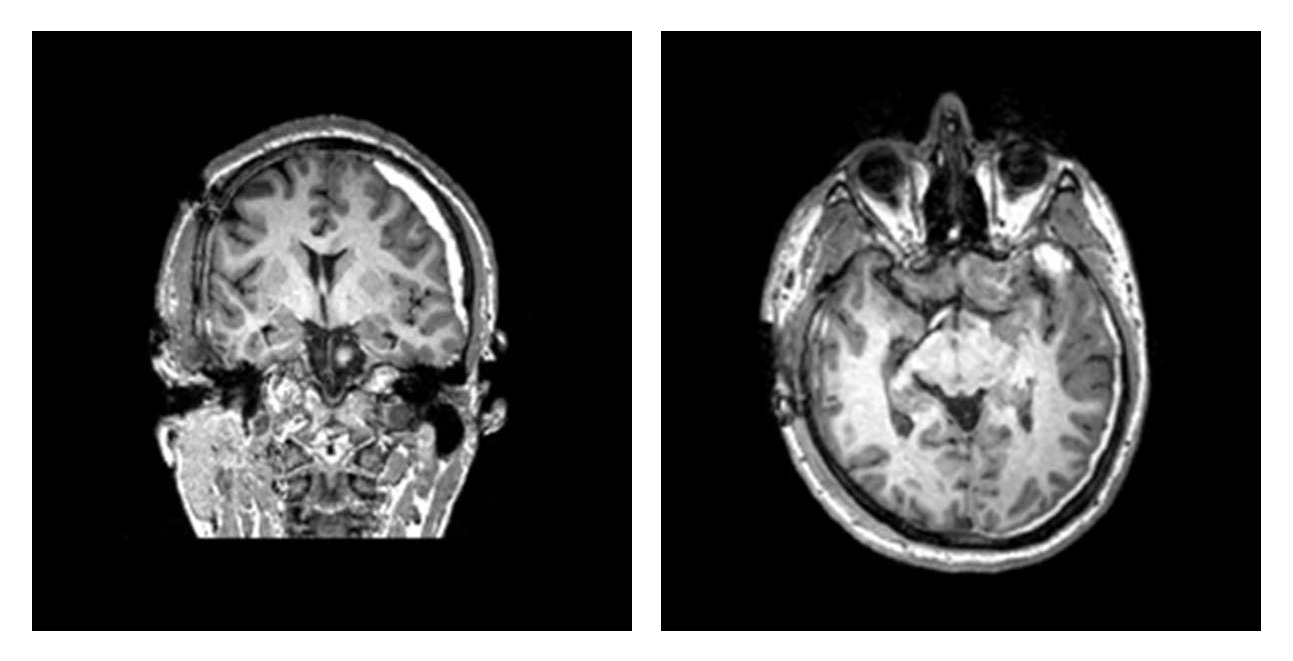

Another study that could help identify patients for the current trial showed that patients with certain patterns of injury that are visible on their CT scans were less likely to make a complete recovery a year later.

Trial participants must enroll on the day of their injury, so they can be treated promptly. They must have a CT scan showing evidence of bleeding, and a blood test and exam that indicate moderate to mild TBI.